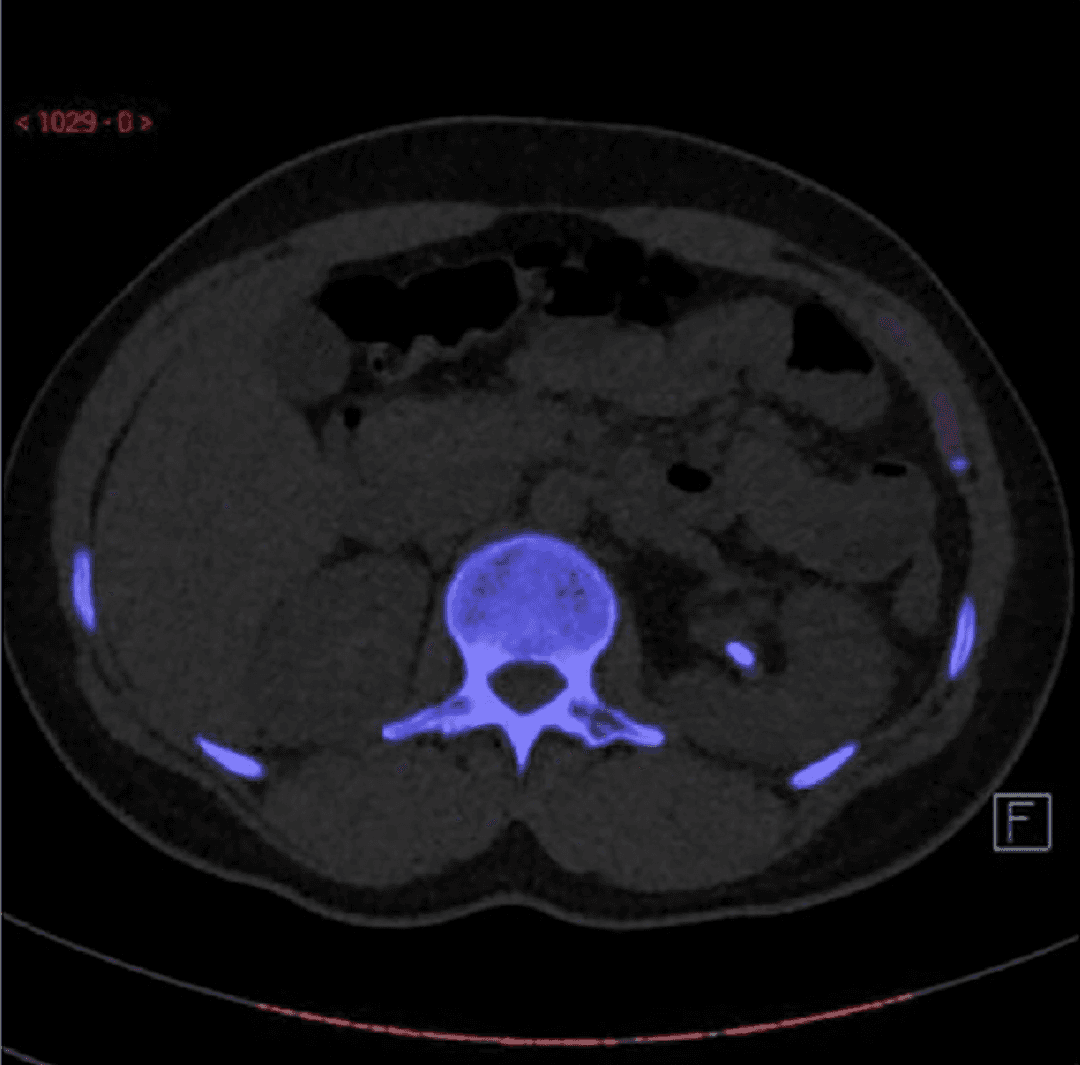

Tomografía computarizada de energía dual (DECT) en corte axial que muestra un cálculo localizado en el uréter proximal derecho, identificado mediante codificación espectral característica de los cálculos de ácido úrico. Esta técnica permite diferenciar de forma no invasiva entre litiasis de ácido úrico y cálculos cálcicos al analizar la atenuación del material a diferentes niveles de energía, información con implicaciones terapéuticas relevantes, ya que los cálculos de ácido úrico pueden responder a tratamiento médico mediante alcalinización urinaria.